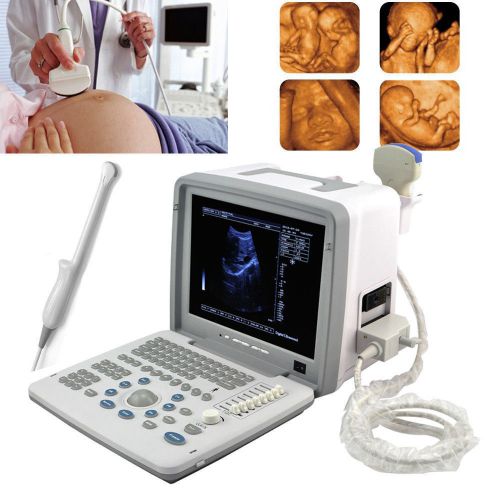

NEW Diagnostic Ultrasound Scanner MACHINE +3D function + convex sensor pregnancy

2015 Digital Laptop Ultrasound Scanner+Convex+ Transvaginal Probe+ 3D image-DHL